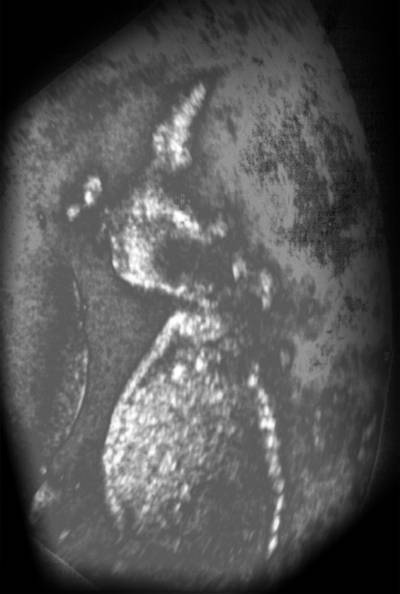

baby in  the fifth month

Baby is now in the fifth month.

If you observe the image closely, you can see two closed fists - one just in front of the nose and the other above the eye holds the umbilical cord. The spinal column is the vertical line on the right. The heart is visible in the middle of the chest - two small areas of light are ventricles.